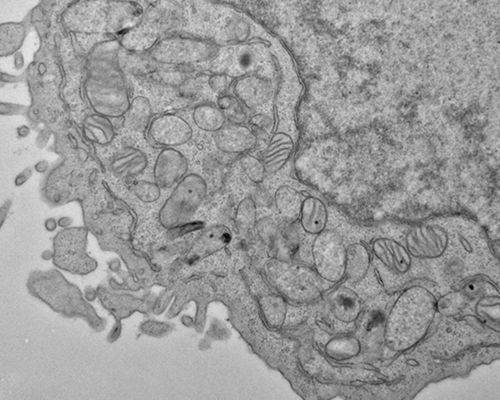

The Metabolomics Platform undertakes both discovery- and hypothesis-driven studies in collaboration with researchers across the Broad and external research communities. Current projects include the discovery of early metabolic markers of predisposition to type 2 diabetes, characterization of mitochondrial disorders, and elucidation of metabolic networks in cellular studies of cancer metabolism, infectious disease, and metabolic disorders.